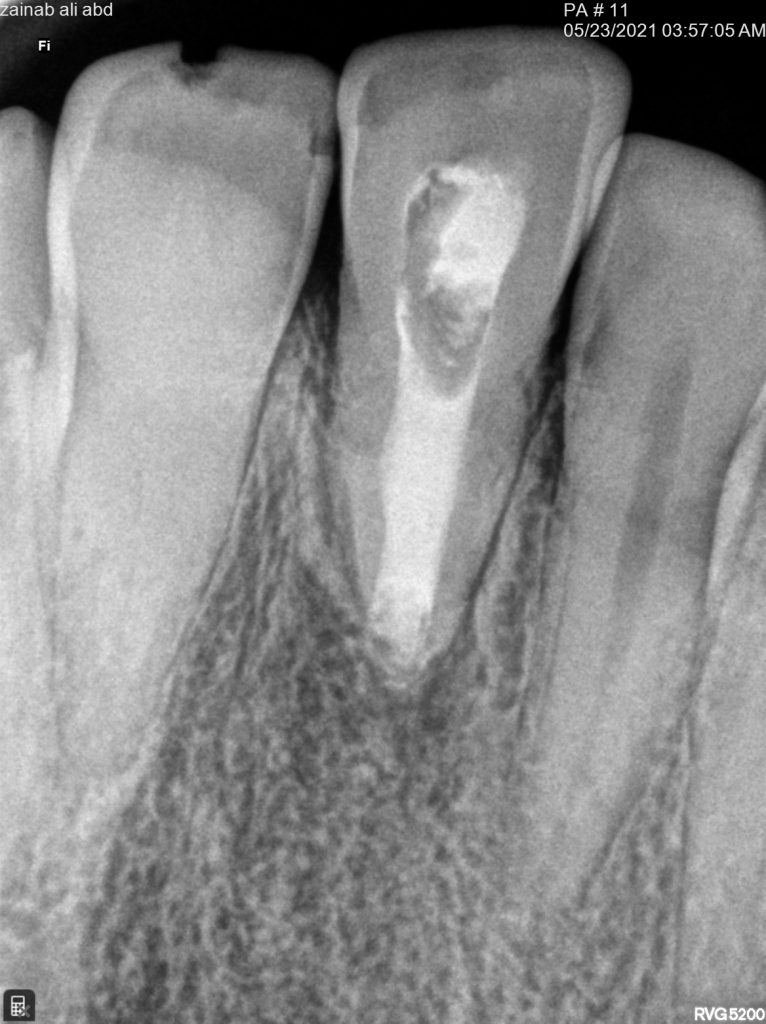

This patient referred to me with sever pain and sinus tract

in the first visit access opening and thorough irrigation with sodium hypochloride till all the pus removed and application of non setting calcium hydroxide for one month

in the second visit the calcium removed and irrigation protocol applied as below

after dryness I applied collagen sponge to control the obturation material from escaping into the apical area

finally filled the canal with bio ceramic putty